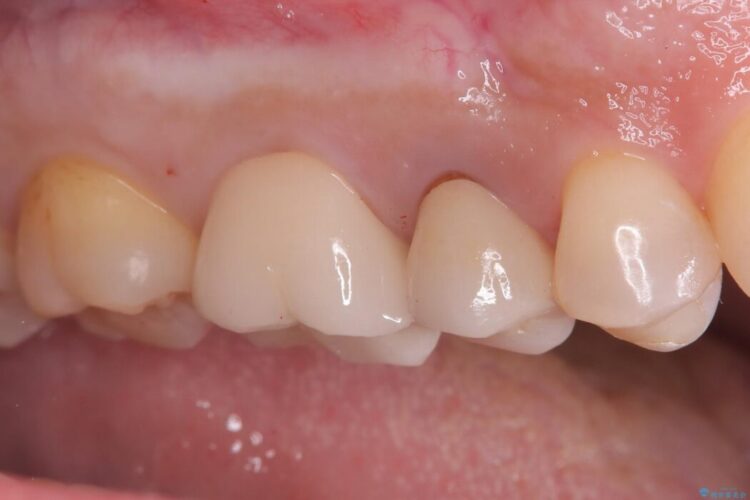

その後、残りの歯を保護して強度を上げるため、適合性が高いオールセラミッククラウンの作成・装着を行いました。

セラミッククラウンは、

強度: 歯全体を覆うため、咬合力による歯への負担を分散させ、破折リスクを大幅に軽減します。

審美性: 天然歯に近い透明感と色調を持つため、銀歯の時と比べて格段に自然で美しい見た目になります。